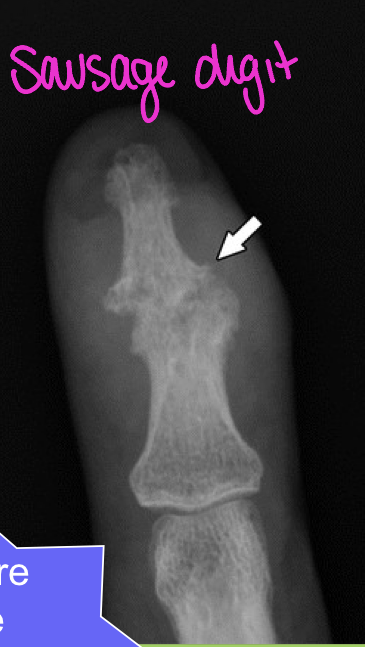

Psoriatic arthritis commonly starts as dramatic effects in

one joint

i.e. erosions that shorten digits (Dactylitis/ Sausage digits)

What finding of PsA is found in this image

central lesions (pencil in cup)

Shortened digit (erosions)